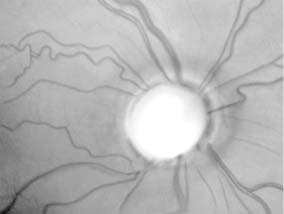

For papilledema to occur, the subarachnoid spaces around the optic nerve must be patent and connect the retrolaminar optic nerve through the bony optic canal to the intracranial subarachnoid space, thus allowing increased intracranial pressure to be transmitted to the retrolaminar optic nerve. There slow and fast axonal transport is blocked, and axonal distention, particularly noticeable at the superior and inferior poles of the optic disk, occurs as the first sign of papilledema. Hyperemia of the disk, dilated surface capillary telangiectases, blurring of the peripapillary disk margin, and loss of spontaneous venous pulsations are the signs of mild papilledema. Edema around the disk can cause a decreased sensitivity to small isopters on visual field testing, but circumferential retinal folds with changes in the internal limiting membrane reflexes (Paton's lines) will eventually become evident as the retina is pushed away from the choked disk; when the retina is pushed away, the blind spot will be enlarged to large isopters on visual field testing as well. In acute papilledema, probably as a consequence either of markedly elevated or rapidly increasing intracranial pressure, there are hemorrhages and cotton-wool spots, indicating vascular and axonal decompensation with the attendant risk of acute optic nerve damage and visual field defects (Figure 14-14). There may also be peripapillary edema (which can extend to the macula) and choroidal folds. In chronic papilledema (new window  Figure 14-15), which is likely to be the consequence of prolonged moderately raised intracranial pressure, a process of compensation appears to limit the optic disk changes such that there are few if any hemorrhages or cotton-wool spots. With persistent raised intracranial pressure, the hyperemic elevated disk gradually becomes gray-white as a result of astrocytic gliosis and neural atrophy with secondary constriction of retinal blood vessels, thus leading to the stage of atrophic papilledema (Figure 14-16). There may also be retinochoroidal collaterals (previously known as opticociliary shunts) linking the central retinal vein and the peripapillary choroidal veins, which develop when the retinal venous circulation is obstructed in the prelaminar region of the optic nerve. (Other causes of retinochoroidal collaterals are central retinal vein occlusion, optic nerve sheath meningioma, optic nerve glioma, and optic nerve head drusen.) Vintage papilledema is characterized by the presence of drusen-like deposits within the swollen optic nerve head.

Figure 14-16

Figure 14-16: Atrophic papilledema in a child with a cerebellar medulloblastoma. The disk is pale and slightly elevated and has blurred margins. The white areas surrounding the macula are reflected light from the vitreoretinal interface. The inferior temporal nerve fiber bundles are partially atrophic (arrows).